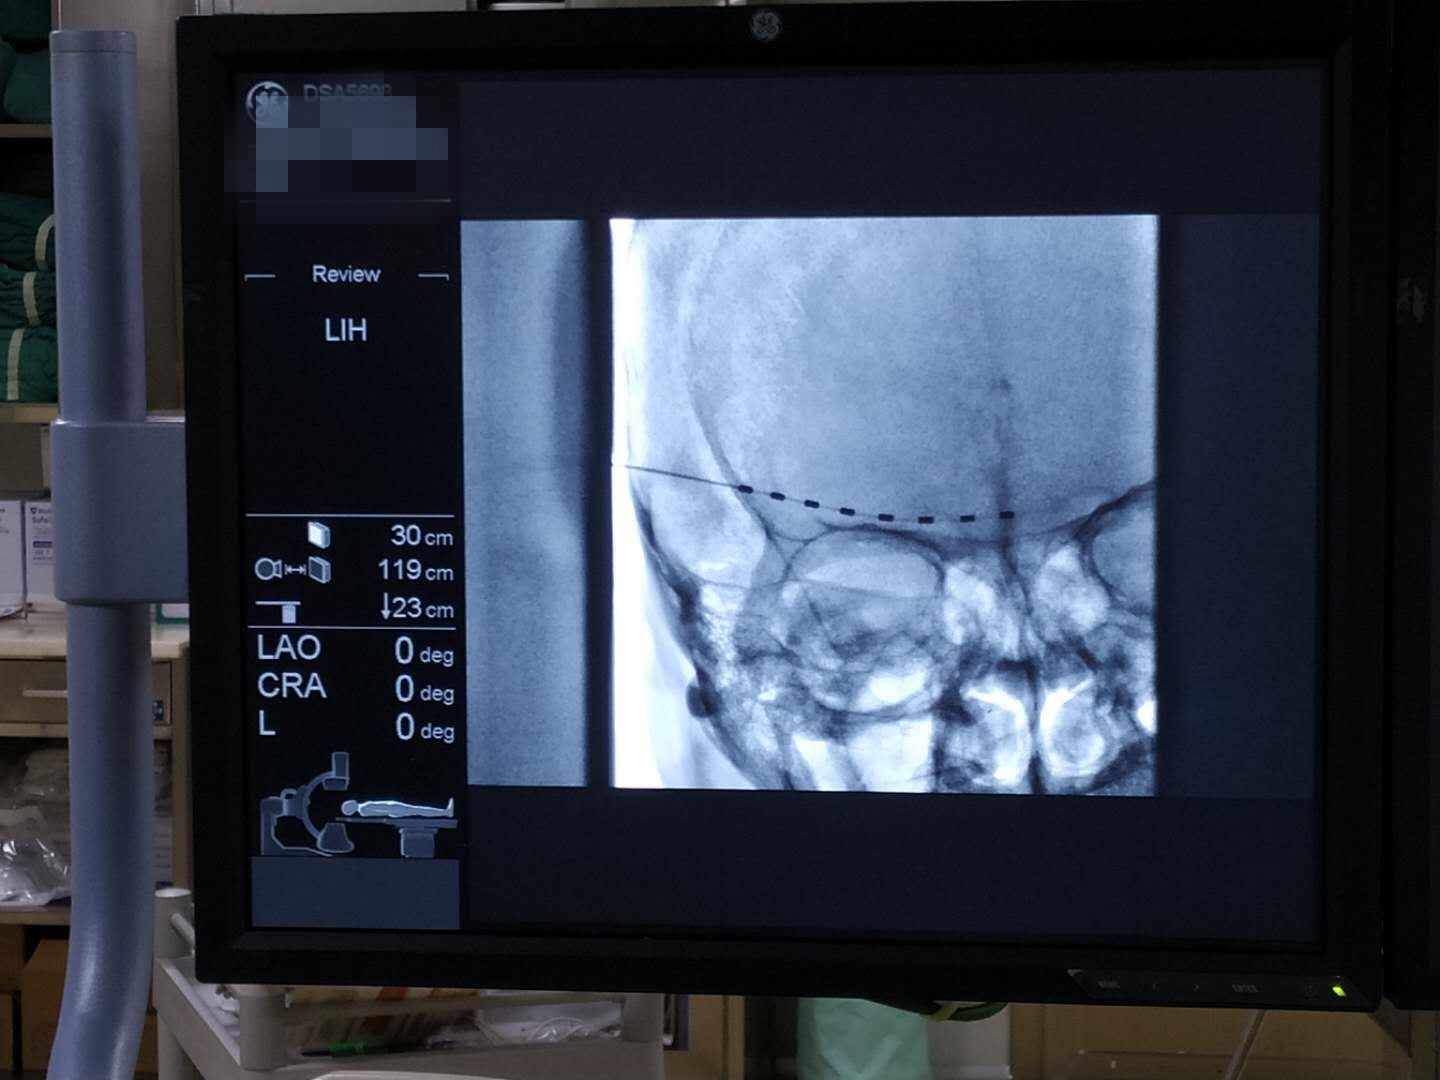

经过了充分准备与耐心沟通,曹启旺主任及团队为张嗲在开展了眶上神经刺激电极植入术,经过9天的持续电刺激治疗后拔除刺激电极,张嗲的疼痛完全缓解、右眼流泪畏光症状消失、视力明显恢复。出院时张嗲嗲感慨道:“早知道我应该一开始就到省人民捷克论坛 疼痛科来看了,就不用受这么多的罪。”